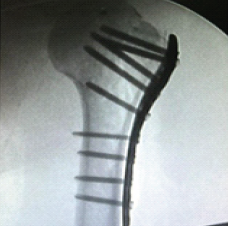

Evaluation of Efficacy of Tranexamic Acid on Blood Loss in Surgically Managed Intertrochanteric Fractures